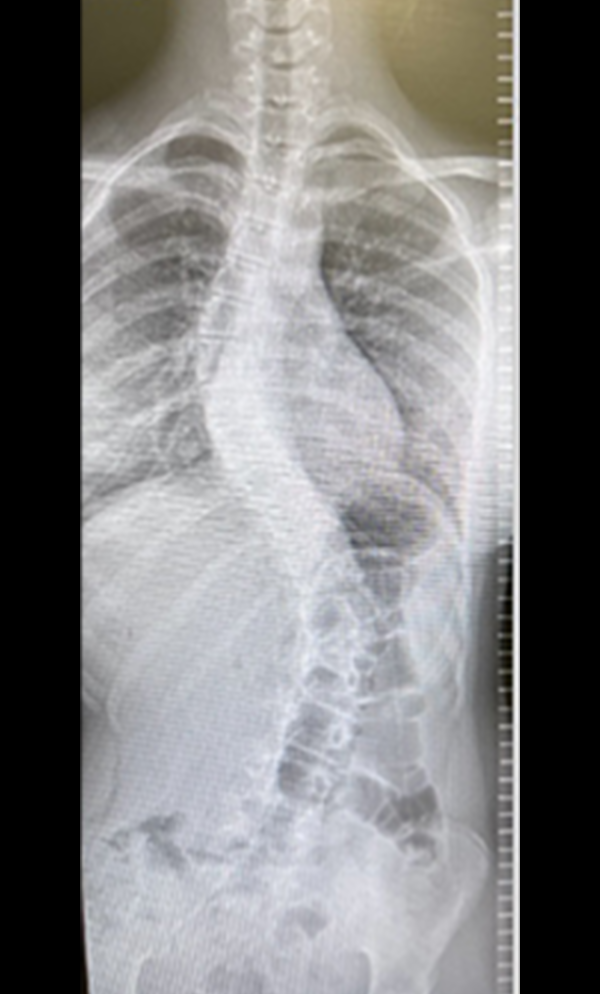

Gallery : Before - After